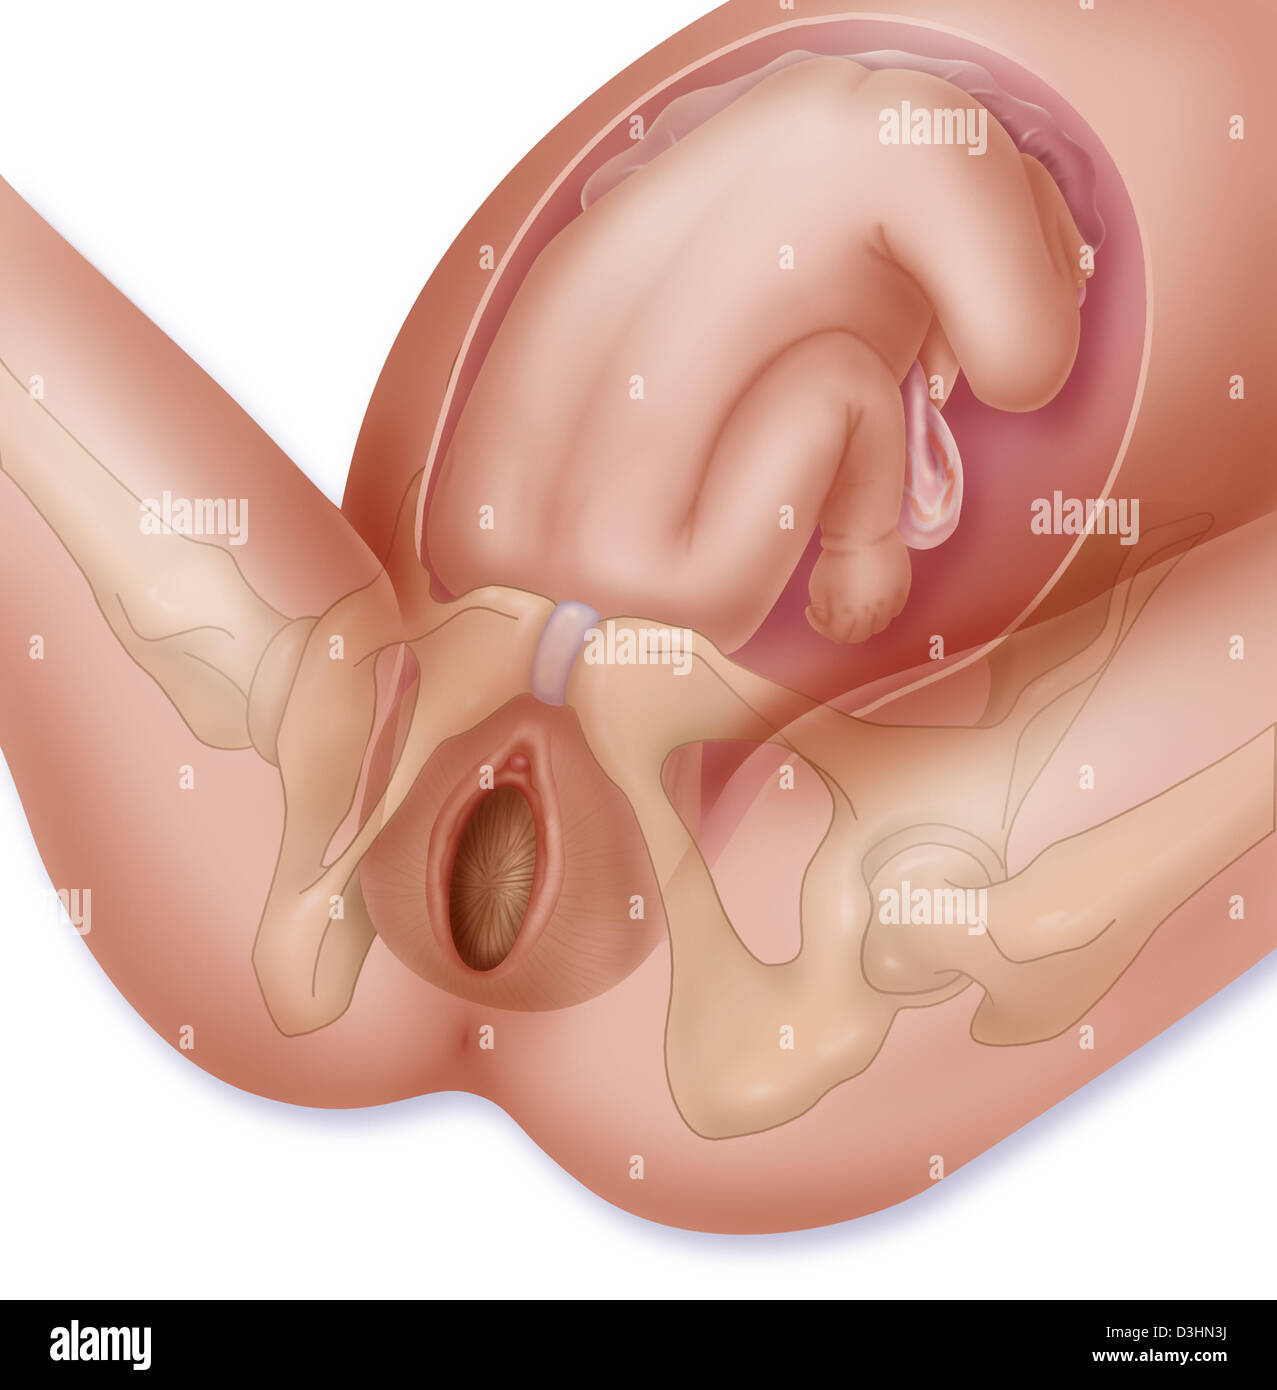

FETAL BREECH PRESENTATION Stock Photohttps://www.alamy.com/image-license-details/?v=1https://www.alamy.com/stock-photo-fetal-breech-presentation-53867030.html

FETAL BREECH PRESENTATION Stock Photohttps://www.alamy.com/image-license-details/?v=1https://www.alamy.com/stock-photo-fetal-breech-presentation-53867030.htmlRFD3HRXE–FETAL BREECH PRESENTATION